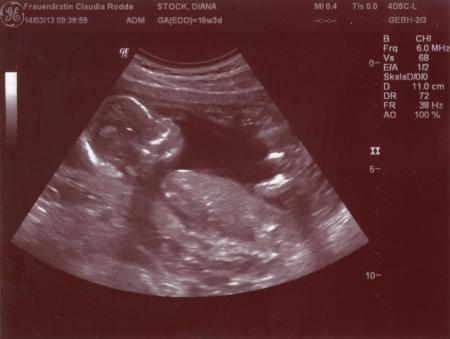

meinem kleinen gehts gut. es sieht aus wie ein affe, find ich ...aber das scheint normal zu sein, da es ja nur aus haut und knochen besteht. hab nicht kucken lassen, was es für ein geschlecht hat. erfahre ich ja sicherlich eh am 10.4. zur FD. bin beruhigt, dass es ihm gut geht, da ich ja letzte woche ziemlich erkältet war.

Ein Affe Das ist ein echt richtig tolles Bild! Nachdem ich im Februar so Krank war (erst Grippe, dann Magen Darm) war ich am 5.3 auch total happy das alles in Ordnung ist!

ja es macht halt nochmal die ganze evulution durch scheinbar ;) war richtig niedlich, hat sich am kopf gekratzt und den mund auf und zu gemacht, als wolle es JA sagen :)

Ich bin voll neidisch auf das gute Schall Gerät :( Bei uns hat man nicht mal das Gesicht so wirklich sehen können nur Umrisse .. Find ich doof dabei bin ich ab Samstag schon in der 19. Woche ... Da musste man doch eig schon was erkennen ... :/

hm, das is wirklich doof. ich hab heut sogar n bissl 3D sehen können. die konnte wohl das gerät da umstellen auf 3D. aber sah halt etwas sehr merkwürdig aus...egal. hauptsache dem kind gehts gut. hat heut nich mal so viel rumgezappelt wie letztes mal. jetzt wieder warten bis zum 5.4.......hach is das lang. aber vielleicht spür ichs ja bis dahin endlich mal.